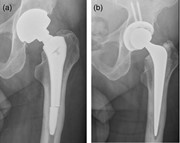

Adverse reaction to metal bearing leading to femoral stem fractures: a literature review and report of two cases

Waheeb A.K. Al-Azzani and others

Journal of Surgical Case Reports, Volume 2016, Issue 2, February 2016, rjw002, https://doi.org/10.1093/jscr/rjw002